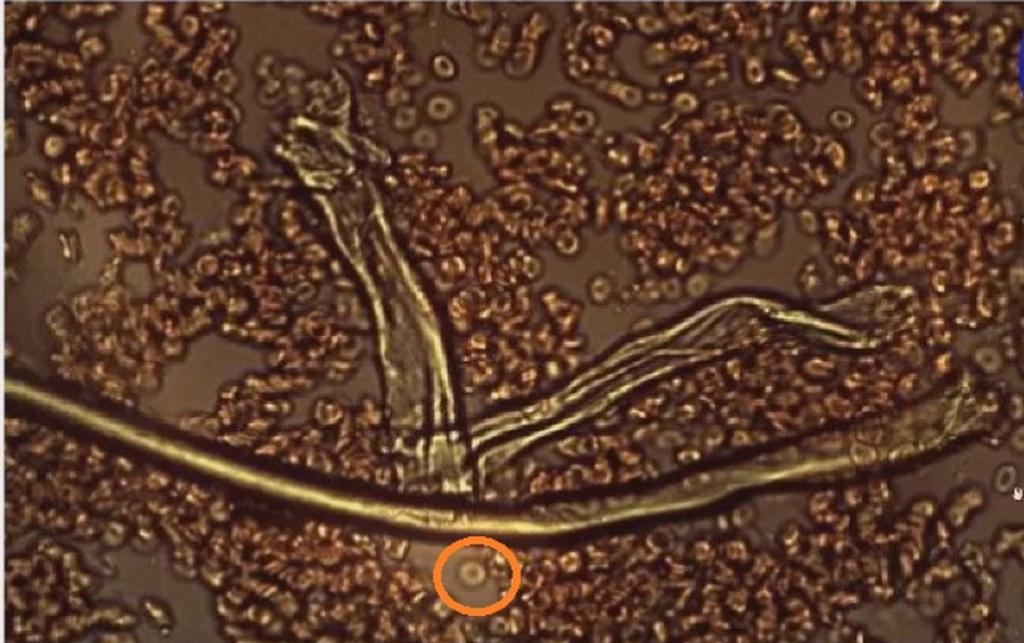

Următoarea imagine este cu sângele unei persoane care a fost injectată cu medicamentul experimental anti-covid. Sângele este coagulat, globulele roșii deformate sunt aglomerate. Celula încercuită în imagine este o globulă roșie sănătoasă, una dintre puținele din imagine, așezată alături de fibrele de grafen. Puteți vedea dimensiunea fibrelor de grafen în raport cu dimensiunea unei celule roșii din sânge. Fibrele de această dimensiune vor bloca capilarele. De asemenea, puteți vedea că fibrele de grafen sunt tubulare și conțin globule roșii.